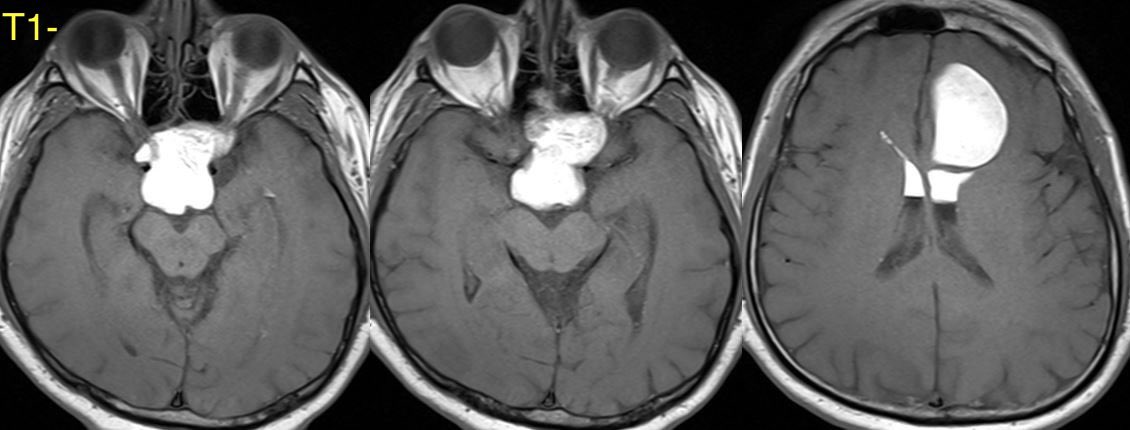

What is the most likely diagnosis in this 30 y/o patient with history of seizures presenting with severe headache?

More images in ๐Ÿงต

Additional images ๐Ÿ‘‡